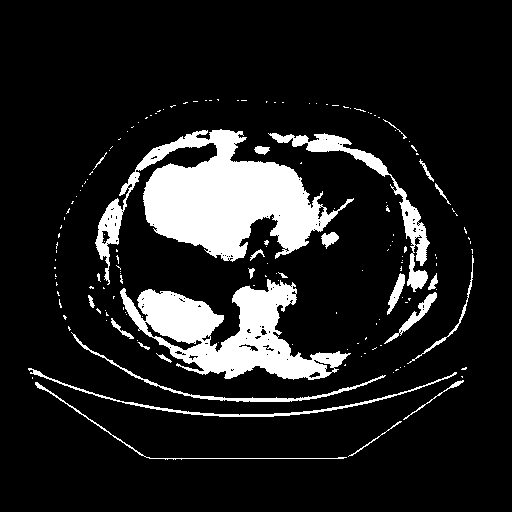

Original VENOUS CT scan

Full window (WL 1023.5, WW 4095 β†’ Low βˆ’1024, High +3071)

Actual HU range: [-1024.0, 3071.0]